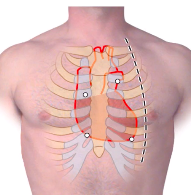

where are the surface anatomy landmarks for the superior, left, right and inferior borders of heart?

outline of the heart:

- inferior border: right border to point close to mid-clavicular line (where get apex beat)

- left border: left inferior to superior margin